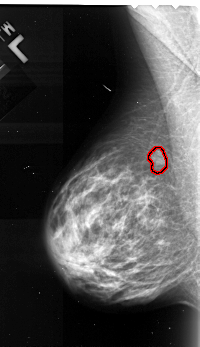

A_1103_1.LEFT_MLO

LEFT_MLO LINES 5191 PIXELS_PER_LINE 2986 BITS_PER_PIXEL 16 RESOLUTION 42 OVERLAY

FILE: A_1103_1.LEFT_MLO.OVERLAY

TOTAL_ABNORMALITIES 1

ABNORMALITY 1

LESION_TYPE MASS SHAPE LOBULATED MARGINS MICROLOBULATED

ASSESSMENT 4

SUBTLETY 4

PATHOLOGY MALIGNANT

TOTAL_OUTLINES 1

BOUNDARY